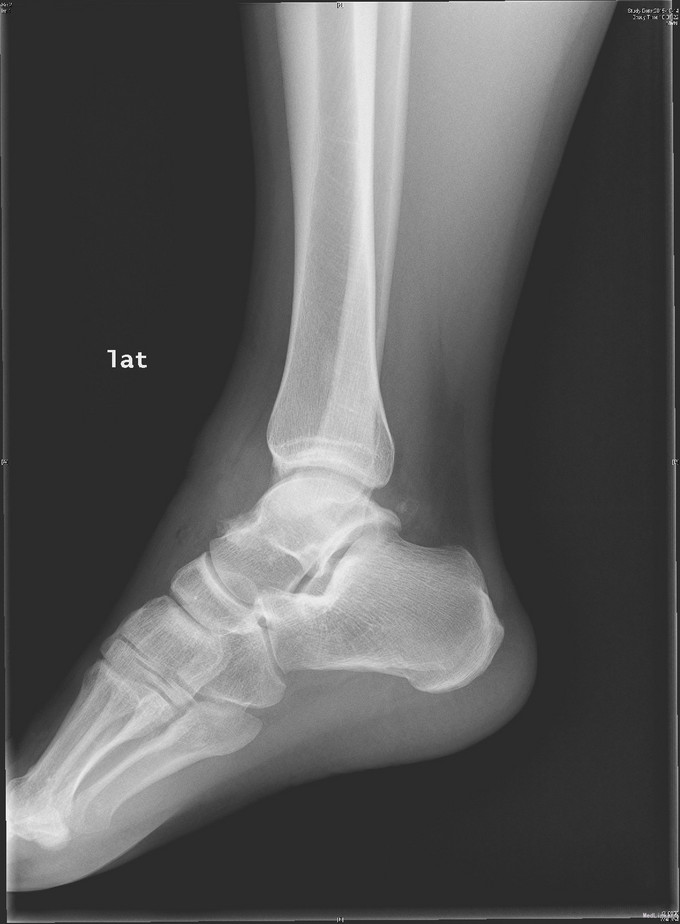

主诉:右踝扭伤后疼痛3年,伴活动受限2年。 现病史:患者男性,24岁。3年前,患者运动时扭伤右踝,无出血。患者当时至外院就诊,予消炎药物保守治疗,疼痛缓解。2年余前患者出现右踝活动受限,以背屈受限明显,伴右踝疼痛,无发热、盗汗,无其它关节痛,无晨僵等。2年来患者自觉右踝疼痛及活动受限症状逐渐加重。外院查MRI示:右胫骨远端前方骨质增生、右距骨前方骨性隆起、右踝关节内积液。我院查右踝X线示:右距骨前下方骨质密度增高、右胫骨前缘骨质增生。于我院就诊,门诊拟"右踝前方撞击综合征、右距骨骨软骨瘤、右踝滑膜炎"收入院。

查体:左下肢、双上肢肌力及活动度正常。右腓肠肌稍萎缩,右踝无明显肿胀。右踝关节跖屈、背屈受限,右踝内侧及前方关节间隙压痛(+)。ADT(-),下蹲提踵试验(+),内翻试验(-)。右腓肠肌肌力、肌张力、感觉正常。 辅查:见现病史。图片见下。

入院诊断:右踝前方撞击综合征、右距骨骨软骨瘤、右踝滑膜炎 治疗:入院完善术前检查后行右踝关节镜下滑膜清理+前方撞击成形+距骨骨软骨瘤切除。